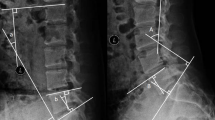

Preoperative Localization: C-arm fluoroscopy was used to identify the surgical segment, including the upper and lower pedicles and intervertebral space (Fig. 1A). A Kirschner Wire (K-wire) was then inserted (Fig. 1B), and a second C-arm fluoroscopy was performed (Fig. 1C and D) to confirm the target segment. The K-wire was ideally positioned at the lower lamina of the upper vertebra and the medial aspect of the facet joints, marking the boundary of the lamina to be resected. In the sagittal plane, the K-wire should align with the center of the target intervertebral disc. If misplaced, the K-wire was repositioned and fluoroscopy repeated.

The application of Kirschner Wire as the location tool before the UBE discectomy. (A) The first fluoroscopy by C-arm to locate the the surgical segment, including the upper and lower pedicles and intervertebral space. (B) Input the Kirschner Wire. C and D. The second fluoroscopy to explore the location of the Kirschner Wire.